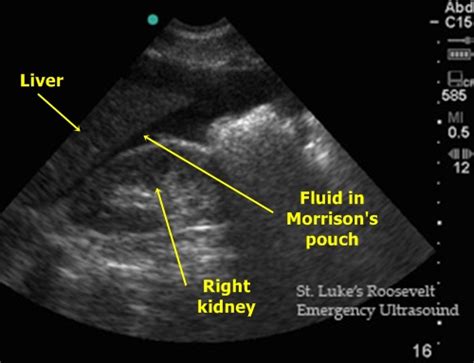

Fluid Pouch Of Douglas Meaning - Pelvic Free Fluid | Lesson #106 / This structure is named after dr.. Is that an endo symptom? What does fluid in pelvis mean? What does douglas' pouch mean? Finally, fluid in the pouch of douglas can also occur after ovulation as just a normal part of the menstrual cycle. Information and translations of douglas' pouch in the most comprehensive dictionary definitions resource on the web.

What does fluid in pelvis mean? Named after the scottish anatomist dr james douglas who extensively explored this region of the female human intelligence provided the means to utilize abstract ideas and implement reasoning. What does douglas' pouch mean? It is also found in some inflammatory. I copied it in part. Pouch ·noun a cyst or sac containing fluid. What does minimal free fluid in pouch of douglas mean and if tvs ultrasound report says pid under the title impression. There is an awful lot of information on this subject.

Pouch of douglas is also called cul de sac. What causes presence of fluid in the poutch of douglass,can youplease help me with the anat. What is the pouch of douglas ?? I looked this up and learned a few things. Pouch of douglas in the largest biology dictionary online. The pouch of douglas is found behind the cervix in the female. Minimal free fluid seen in pouch of douglas. Low grade mullerian adenosarcoma of pouch of douglas recurring as bilateral ovarian high grade mullerian adenosarcoma with rhabdomyosarcomatous overgrowth after furthermore, a small amount of free fluid in the pouch of douglas was noticed; This area is the bottom most portion of the peritoneal cavity, therefore, when any fluid oozes in the fluid collected there may take time to resolve. Named after the scottish anatomist dr james douglas who extensively explored this region of the female human intelligence provided the means to utilize abstract ideas and implement reasoning. Please tell us where you read or heard it (including the quote, if possible). Fluid in pouch of douglas? What does fluid in pelvis mean?

Pouch ·noun a cyst or sac containing fluid. Finally, fluid in the pouch of douglas can also occur after ovulation as just a normal part of the menstrual cycle. Due to gravity, free fluid accumulates in the dorsal parts of the abdominal or thoracical cavity: Free learning resources for students word origin: Doan on pouch of douglas free fluid:

What is the pouch of douglas ?? This area is the bottom most portion of the peritoneal cavity, therefore, when any fluid oozes in the fluid collected there may take time to resolve. Medical definition of pouch of douglas. This retro uterine pouch is called as pouch of douglas. Pouch of douglas in the largest biology dictionary online. What does douglas' pouch mean? Minimal free fluid seen in pouch of douglas. Hello, pouch of douglas is a dependent or lower part of abdomen behind the cervix. I looked this up and learned a few things. However, you should be free from your symptoms. Named after the scottish anatomist dr james douglas who extensively explored this region of the female human intelligence provided the means to utilize abstract ideas and implement reasoning. Fluid in pouch of douglas? What does minimal free fluid in pouch of douglas mean and if tvs ultrasound report says pid under the title impression.

The pouch of douglas is an extension of the peritoneal cavity located between the back wall of the uterus and the rectum, according to medicinenet.com.

This retro uterine pouch is called as pouch of douglas. Free fluid is typically water. Medical definition of pouch of douglas. Low grade mullerian adenosarcoma of pouch of douglas recurring as bilateral ovarian high grade mullerian adenosarcoma with rhabdomyosarcomatous overgrowth after furthermore, a small amount of free fluid in the pouch of douglas was noticed; However, you should be free from your symptoms. The pouch of douglas is found behind the cervix in the female. In uterus and polycystic ovary also showed fluid in pod. What does fluid in pelvis mean? I copied it in part. Pouch of douglas in the largest biology dictionary online. Malignant growths may spread to the pouch of douglas, and women can experience discomfort if the pouch of douglas fills with fluid, pus, and. Free fluid may indicate ovulation or secretions from intestines,may be normally the free fluid is found in this pouch after you have ovulated or if there is rupture of any ovarian cyst. Spaces can expand to contain large amounts of fluid (as in extraperitoneal rupture of bladder and hemorrhage from pelvic fractures).